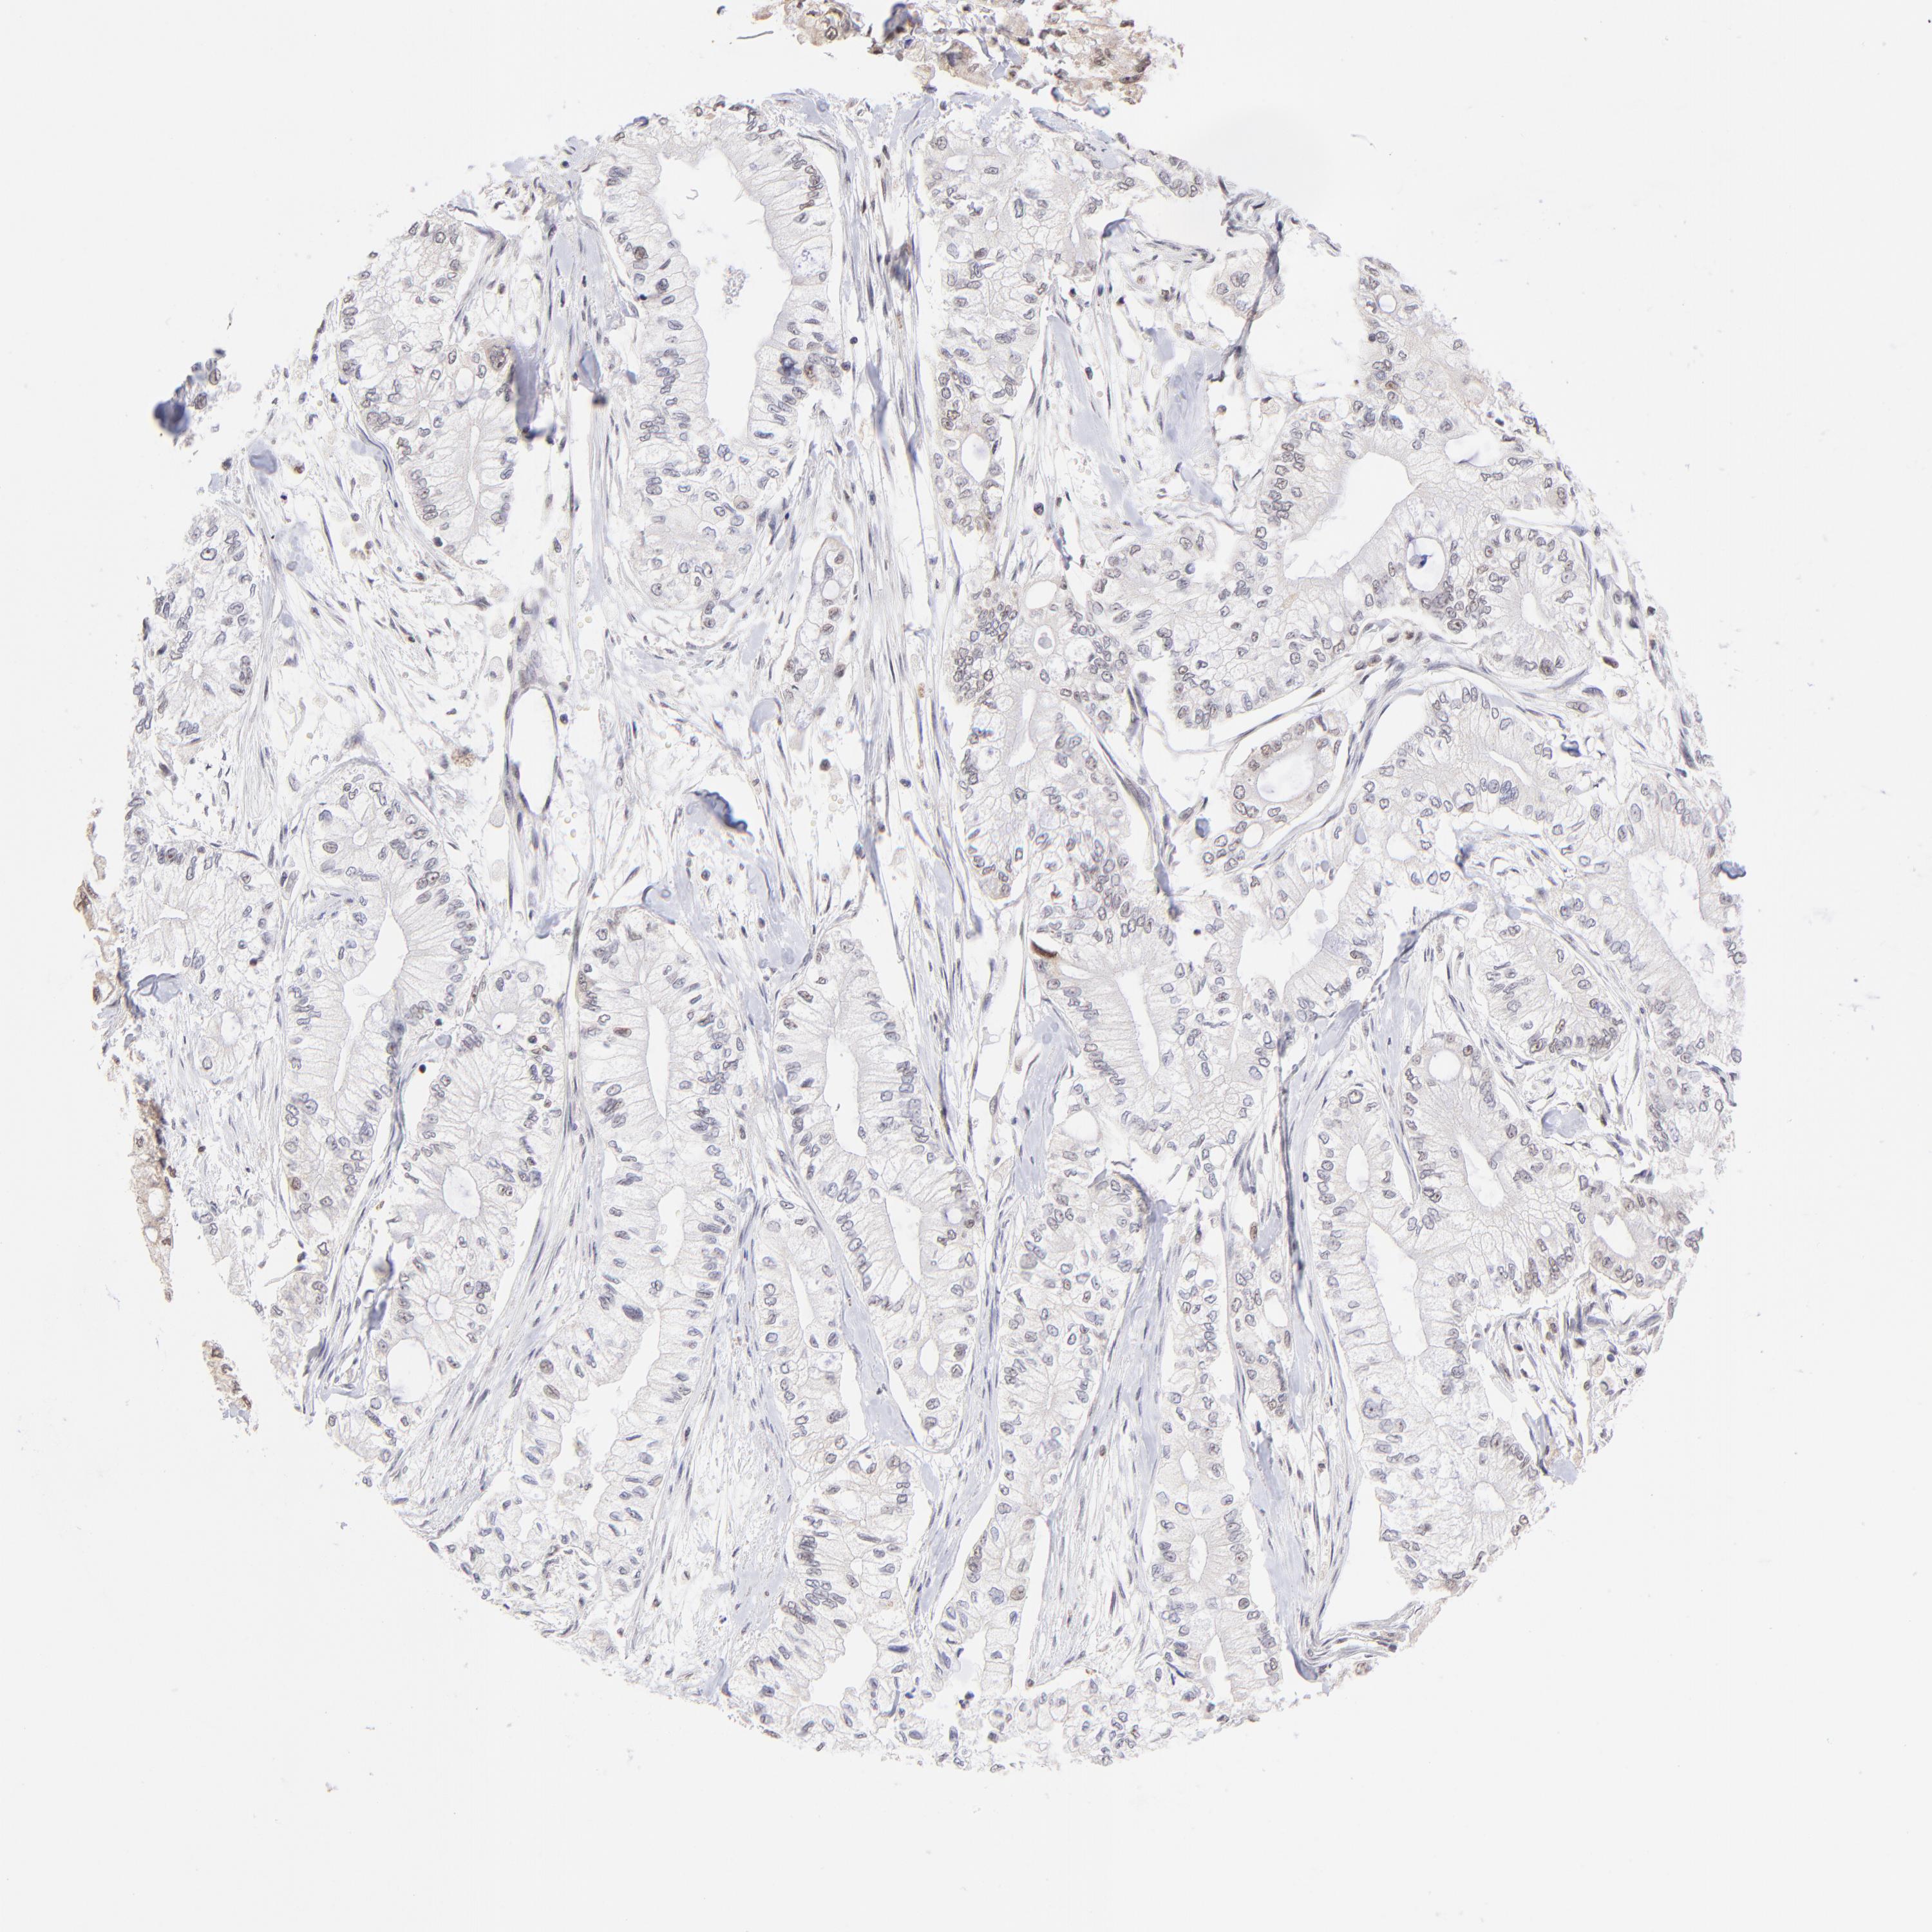

PANCREATIC CANCER - Protein expressioni

A mouse-over function shows sample information and annotation data. Click on an image to view it in a full screen mode. Samples can be filtered based on level of antibody staining by selecting one or several of the following categories: high, medium, low and not detected. The assay and annotation is described here.

Note that samples used for immunohistochemistry by the Human Protein Atlas do not correspond to samples in the TCGA dataset.

Antibody stainingi

Antibody staining in the annotated cell types in the current human tissue is reported as not detected, low, medium, or high, based on conventional immunohistochemistry profiling in selected tissues. This score is based on the combination of the staining intensity and fraction of stained cells.

Each image is clickable and will lead to virtual microscopy that enables deeper exploration of all samples and also displays staining intensity scores, fraction scores and subcellular localization as well as patient and tissue information for each sample.

Antibody HPA003142

Staining

High

Medium

Low

Not detected

Intensity

Strong

Moderate

Weak

Negative

Quantity

>75%

75%-25%

<25%

None

Location

Nuclear

Cytoplasmic/membranous

Cytoplasmic/membranous,nuclear

Adenocarcinoma, NOS